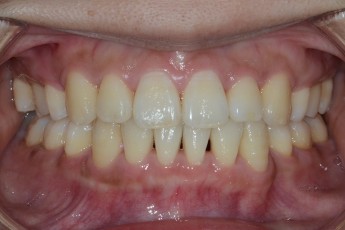

BEFORE & AFTER